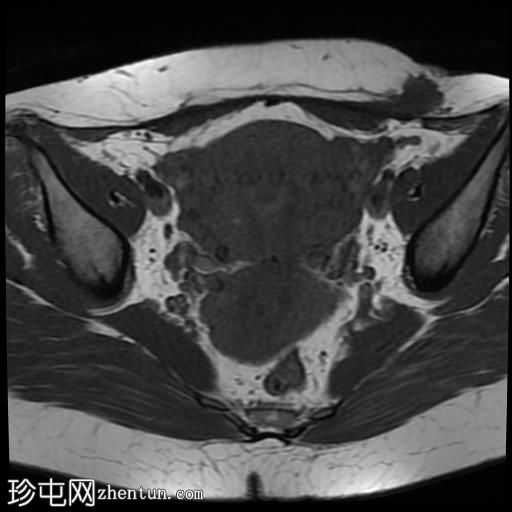

轴位

T1加权像

轴位T1加权像

左侧腹直肌和腹内斜肌前缘旁可见一边界不清的深部皮下软组织肿块。T1加权像呈等信号,T2加权像呈中低信号,增强扫描呈中度不均匀强化。

可见微小的肌壁内平滑肌瘤。

未见卵巢或腹膜下子宫内膜异位症。

临床表现和MRI特征最符合剖宫产瘢痕子宫内膜异位症。